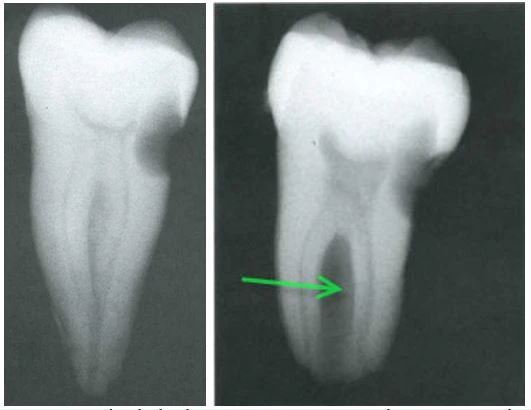

Hầu hết các CS đều dính nhau ở mặt ngoài ,mặt trong là một rãnh sâu chạy từ thân răng xuống tới chóp . Chính điều này giải thích tại sao trên film cận chóp thường thấy rõ hai chân răng ,nhưng vùng giữa 2 chân chỉ hơi cản quang một chút ,có ít bè xương vì sensor luôn được đặt phía mặt trong. Không phải lỗ ống tủy nào của CS cũng đều có ống tủy riêng,chỉ có 34,2 % lỗ ống tủy có ống tủy riêng đi tới chóp,còn hầu hết các lỗ ống tủy đều nhập với các ống tủy khác. Tỷ lệ CS trên người Châu Á khá cao,nên khi nhìn thấy trên film một răng cối nhất là R7 dưới có chân chụm ,ở giữa 2 chân có một vùng cản quang ít thì nên cảnh giác.